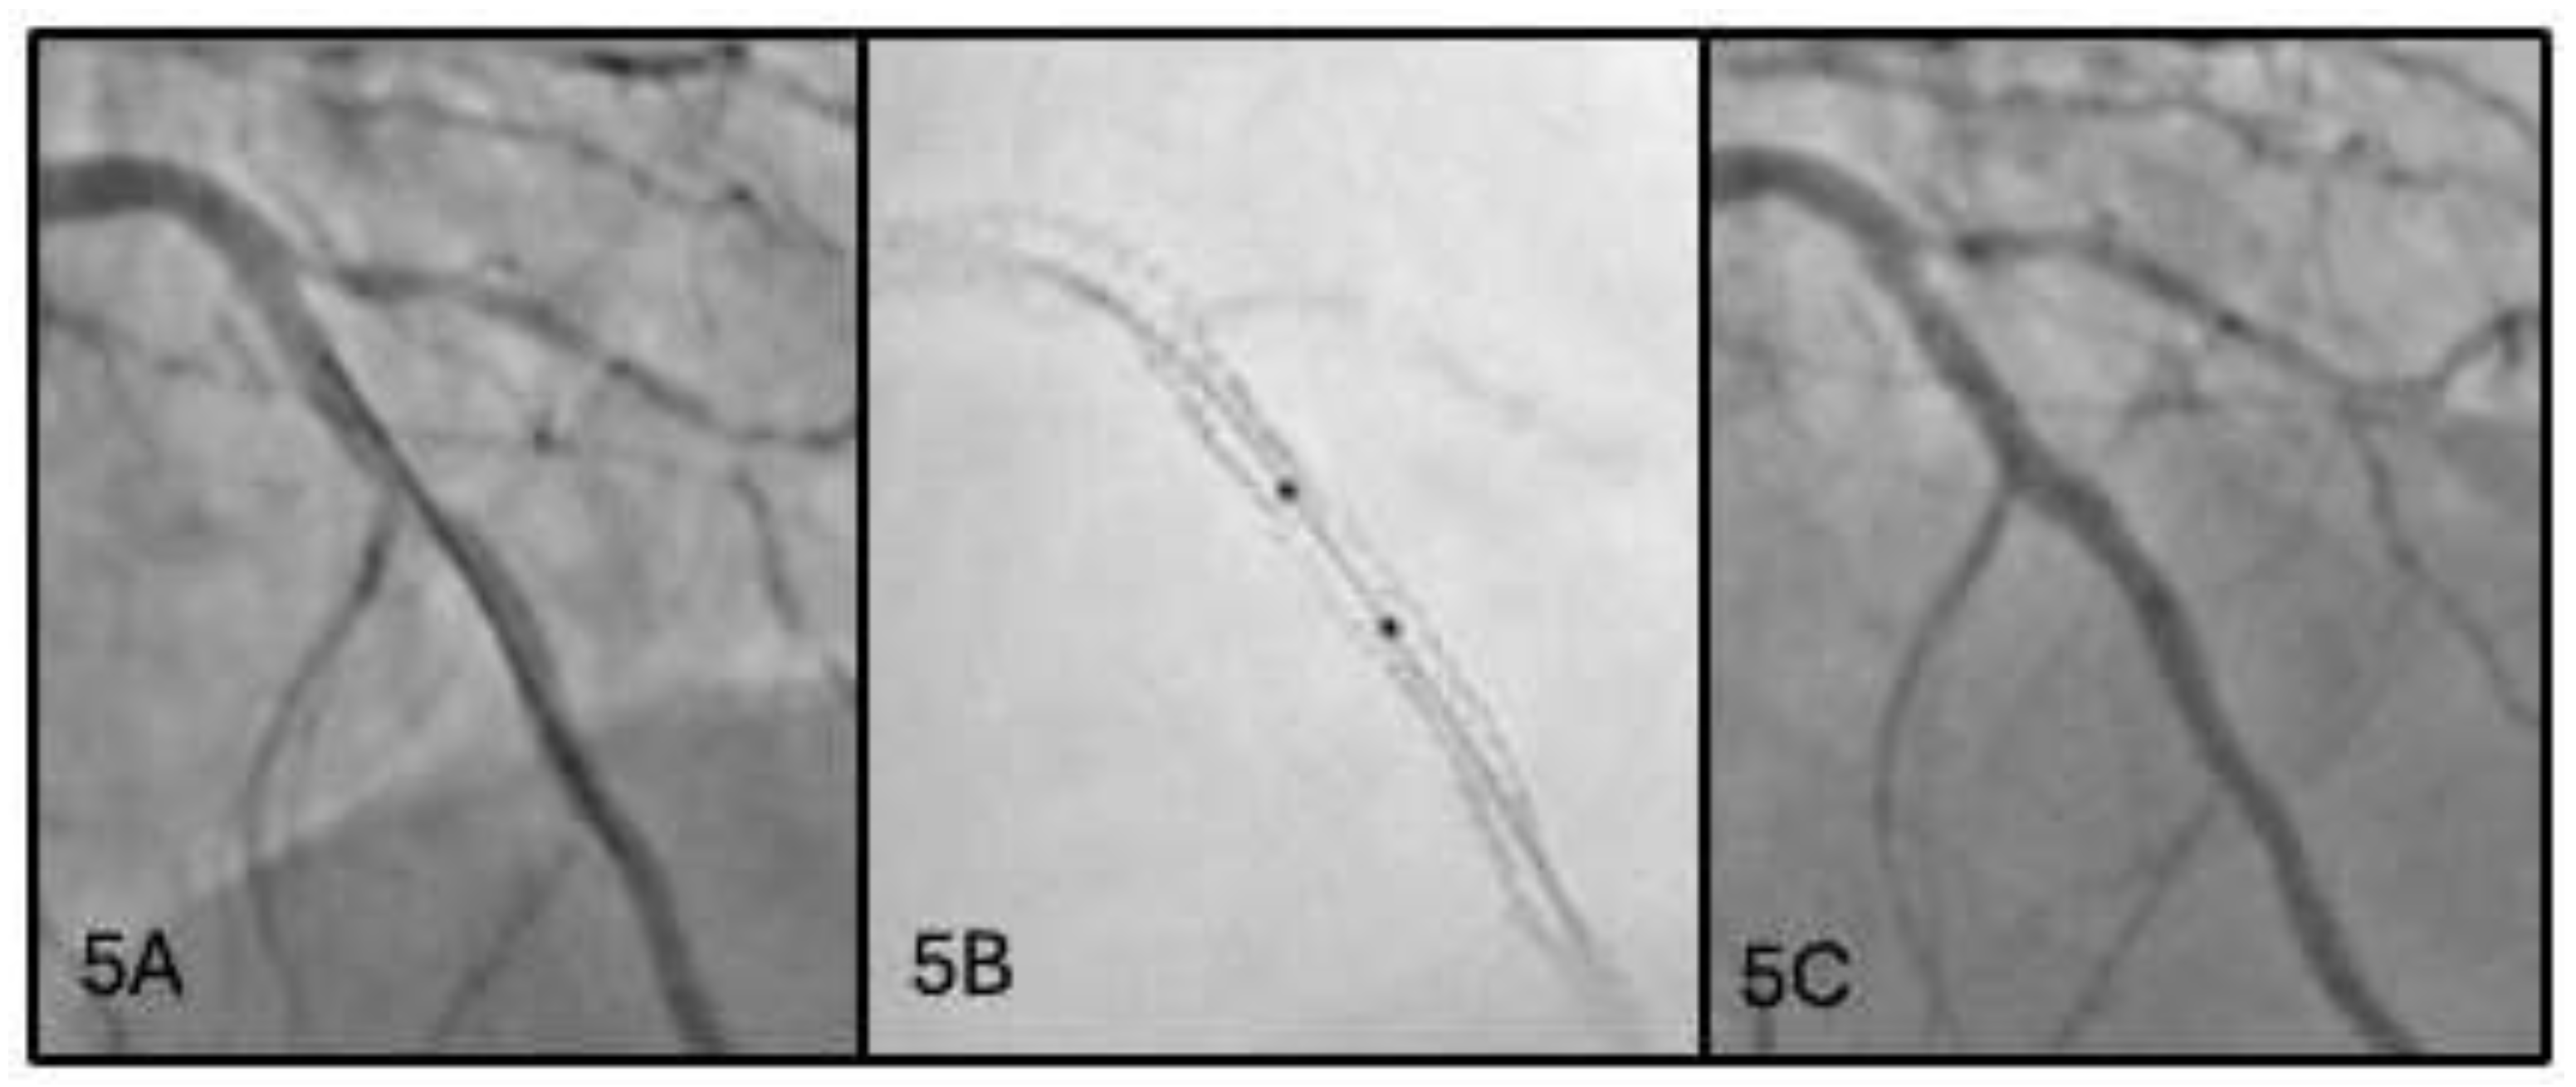

2.5. Fifth Scenario: Missed Overlap